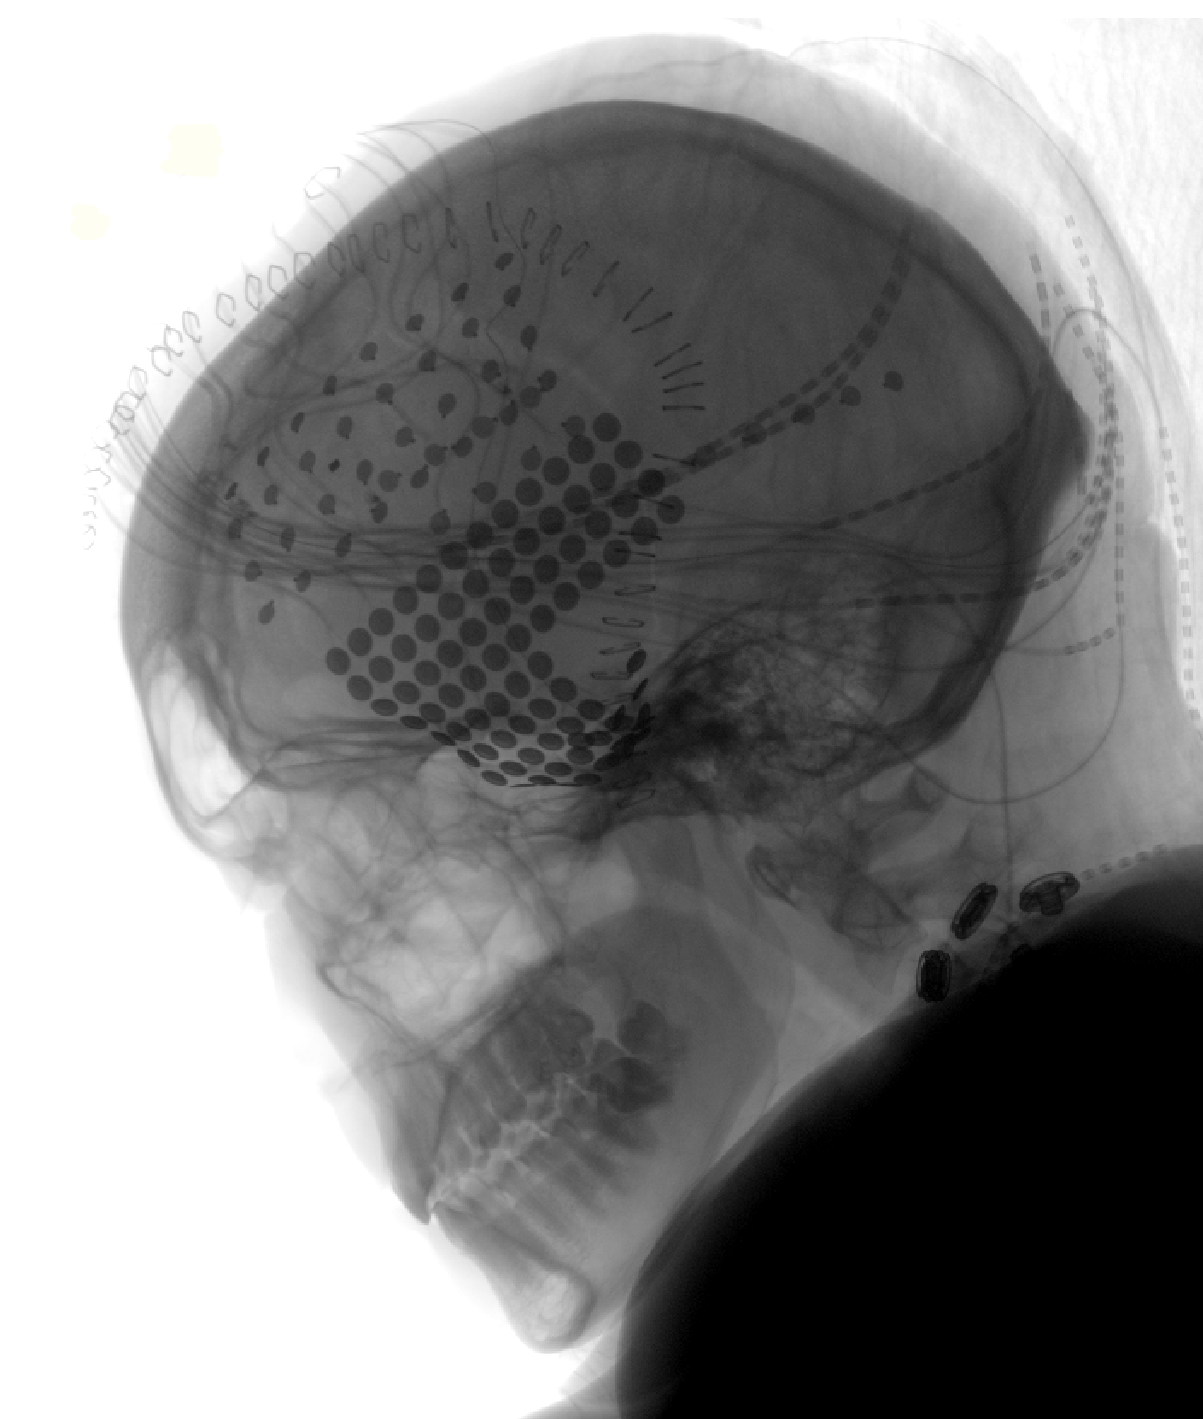

As the chords of Pink Floyd's “Another Brick in the Wall, Part 1,” filled the hospital suite, neuroscientists at Albany Medical Center diligently recorded the activity of electrodes placed on the brains of patients being prepared for epilepsy surgery.

Because these intracranial electroencephalography (iEEG) recordings can be made only from the surface of the brain — as close as you can get to the auditory centers — no one will be eavesdropping on the songs in your head anytime soon.

Bellier emphasized that the study, which used artificial intelligence to decode brain activity and then encode a reproduction, did not merely create a black box to synthesize speech. He and his colleagues were also able to pinpoint new areas of the brain involved in detecting rhythm, such as a thrumming guitar, and discovered that some portions of the auditory cortex — in the superior temporal gyrus, located just behind and above the ear — respond at the onset of a voice or a synthesizer, while other areas respond to sustained vocals.